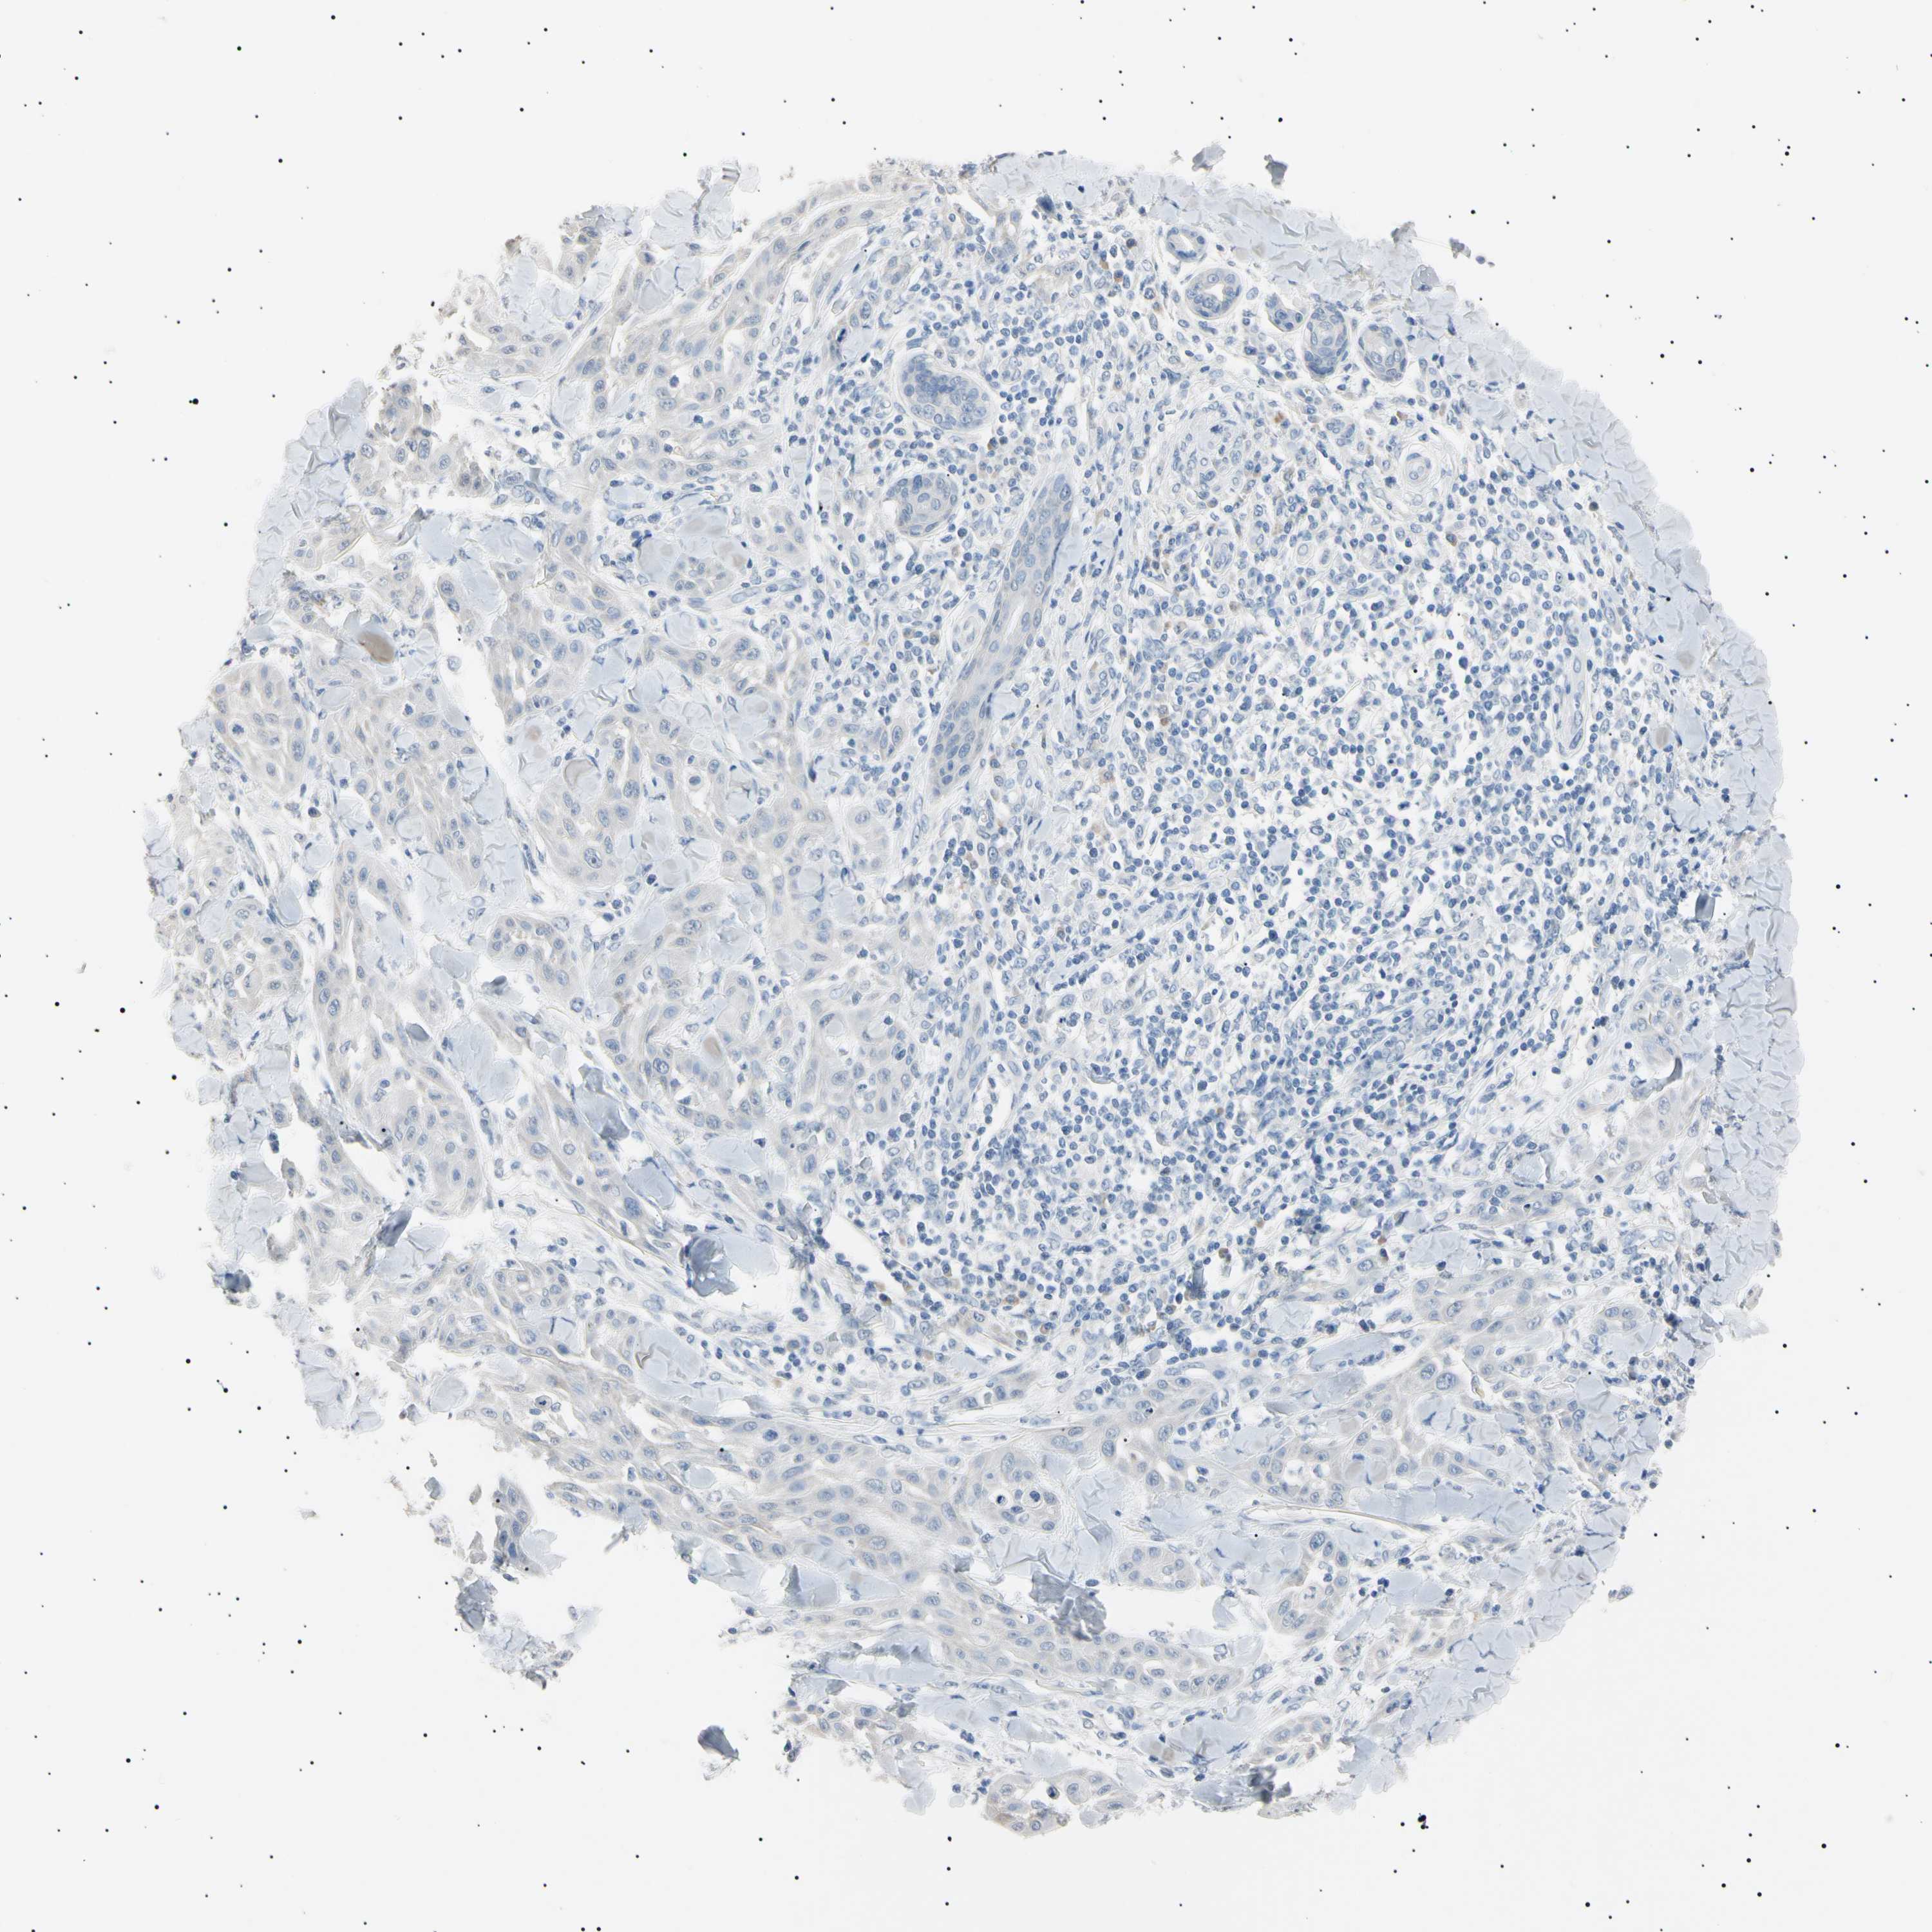

SKIN CANCER - Protein expressioni

A mouse-over function shows sample information and annotation data. Click on an image to view it in a full screen mode. Samples can be filtered based on level of antibody staining by selecting one or several of the following categories: high, medium, low and not detected. The assay and annotation is described here.

Each image is clickable and will lead to virtual microscopy that enables deeper exploration of all samples and also displays staining intensity scores, fraction scores and subcellular localization as well as patient and tissue information for each sample.

Antibody CAB010884

Squamous cell carcinoma, NOS